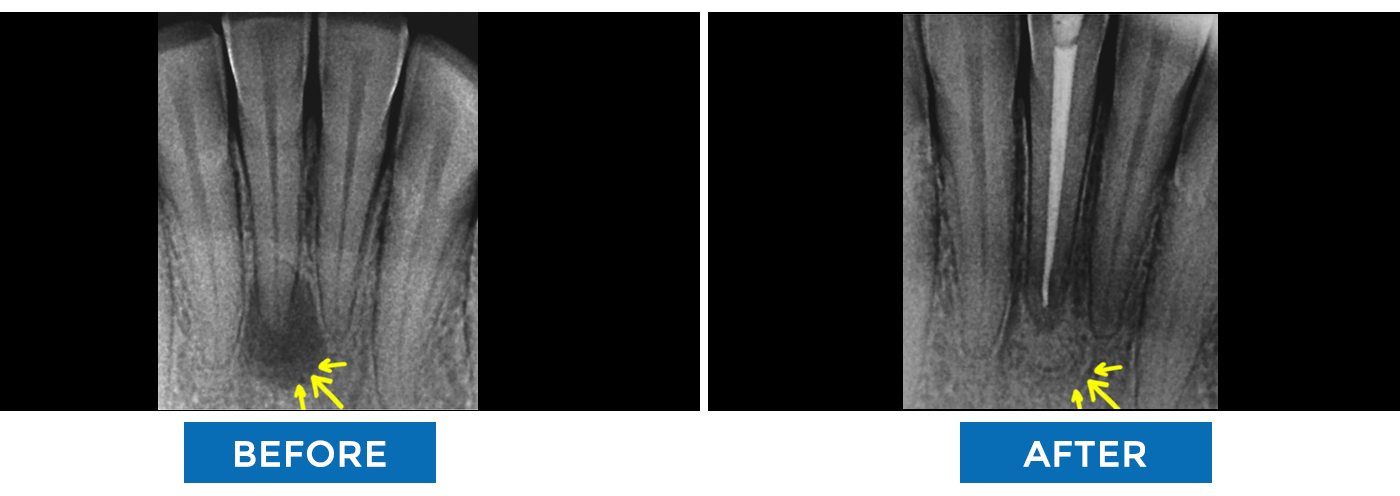

Bone Defect Completely HEALED after ROOT CANAl TREATMENT (RCT)